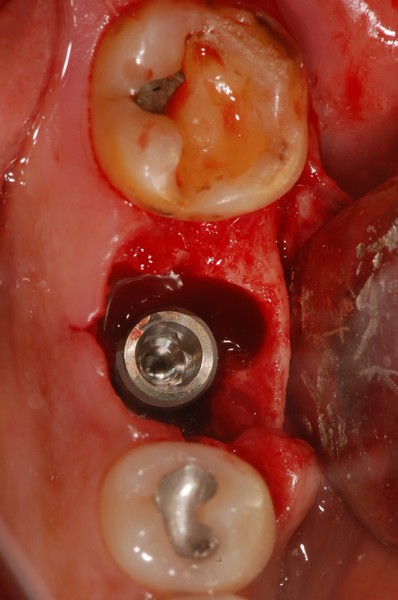

그 다음으로

이를 뽑고 난 자리에

인공치근을 심는 과정이 이루어지는데,

뿌리가 있던 자리와 인공치근 사이에는

빈 공간이 생깁니다.

그 틈을 메우기 위해

인공뼈(골이식재)를 함께 채워

임플란트가 단단히 자리 잡을 수 있도록 하는

과정이 필요합니다.